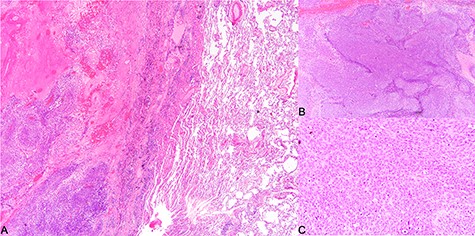

Histological findings. (A) Tumor invading into lung parenchyma, (B) tumor arranged in solid sheets (×40) and (C) tumor cells of the poorly differentiated hepatocellular carcinoma (×200).